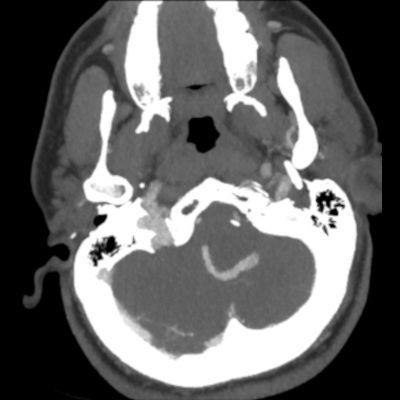

- B. Kontrastsız BT incelemede heterojen dansitede, perferinde kaba kalsifikasyon gösteren kitle lezyonu (ok), BT anjiografi MIP aksiyal kesitte yılan gibi eksantrik bir açık damar görülmektedir (ok). Sağ posterior inferior serebellar arterden (PICA) doluş gösteren tortiyoze dilate vasküler yapı (ok) DSA’ da demonstre edilmiş.

- BT

- Heterojen yoğunlukta, yuvarlak veya oval kitle lezyonları olarak görülür.

- Kısmen tromboze oldukları için, lezyon içinde farklı evrelerde kan ürünleri izlenebilir.

- BT anjiyografi (BTA) ile anevrizma içindeki patent, serpantin damar kanalı ve anevrizmanın besleyici damarları daha net bir şekilde görüntülenebilir.

- Kitle etkisi ve çevre dokularda ödem de BT’de görülebilen bulgulardandır.